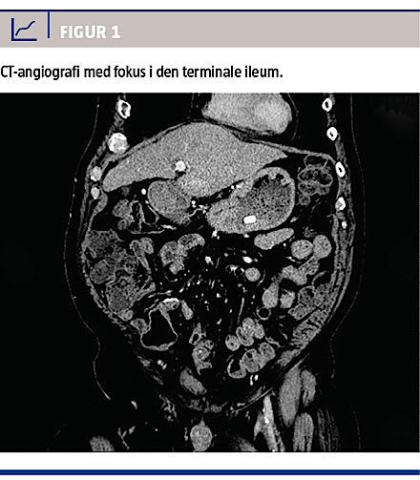

På mistanke om atrioventrikulær malformation supplerede man med en blødningsscintigrafi, som viste blødningsfokus i den terminale ileum. Retrospektivt kunne dette også ses på CT-angiografien (Figur 1). Da patienten var ude af sin koma og forventedes at kunne overleve kirurgi, fandt man ved laparotomi en venøs forbindelse fra en varicøs, umbilikal vene til den terminale ileum, hvor der var varicer. Man foretog tyndtarmsresektion af det afficerede område med anlæggelse af en primær anastomose. Det postoperative forløb var ukompliceret, og patienten gik på en længere orlov efter syv dage og havde fire måneder efter ikke været indlagt igen. Patologisvaret bekræftede, at der var tale om varicer i den terminale ileum.